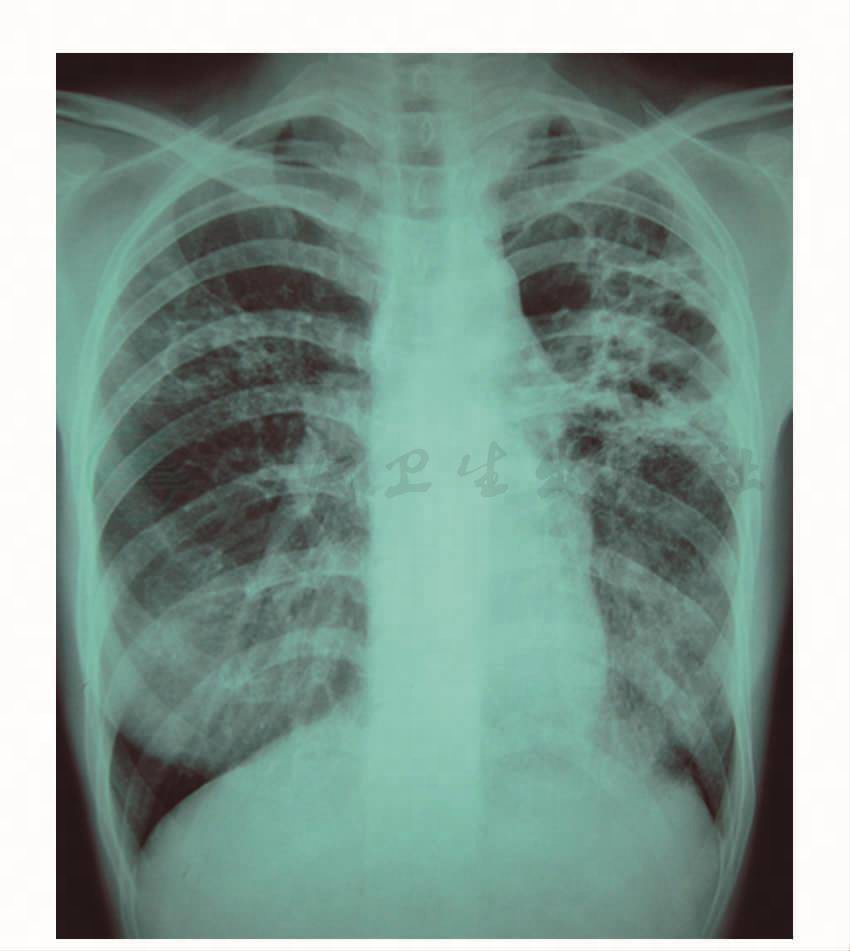

图1 胸片(2008年6月25日):肺部炎症

图2 胸片(2008年7月2日):两肺炎性病变加重

患者于2008年6月起无明显诱因出现咽痛,开始为说话时咽部不适感,于当地医院就诊,胸片检查提示肺部炎症(图1),予抗感染治疗6天后复查胸片(图2)未见好转,反见加重。拟诊为“肺结核”,于2008年7月2日开始给予利福喷汀、乙胺丁醇、帕司烟肼三联抗结核治疗2个月,其间曾因出现肝功能损害,停用抗结核药并护肝治疗1周后继续抗结核治疗。治疗后,患者咽痛症状无改善,呈进行性加重,严重时吞咽疼痛影响进食,先后于2008年8月、2008年9月两次复查胸片未见好转,行胸部CT检查示双肺弥漫性磨玻璃样病变(图3),又开始给予利福喷汀、乙胺丁醇、链霉素、左氧氟沙星四联抗结核治疗。治疗2个月后(2008年11月),患者症状无改善,复查胸部CT提示病变范围明显增加(图4)。遂于2008年12月转至上级医院就诊,行咽组织活检,病理见多核巨细胞、上皮样细胞构成的结核样结节,未见典型干酪样坏死,考虑增殖型结核可能性大;继续抗结核治疗,同时超声雾化吸入“异烟肼、链霉素”治疗2周。此后(2009年1月)患者开始出现咳嗽,多见于早晨,开始为阵发性单声咳,后咳嗽加剧,为持续性,伴咳白色泡沫痰,偶痰中见血丝,伴轻度活动后气促。遂到某结核病专科医院就诊,复查胸片考虑双侧上、中、下肺野结核并双上肺空洞(图5)。继续抗结核治疗,1个月后(2009年2月)复查胸片提示病灶较前有吸收,空洞缩小(图6)。但患者症状无好转,2个月后复查胸片提示“双肺病灶增多,左上肺空洞增大”(图7)。于该院住院,纤维支气管镜活检病理见由上皮样细胞和朗格汉斯细胞组成的结核样结节,未见干酪样坏死。入院约1周后胸部CT检查提示双肺病变较前有所减少(图8)。2009年5月患者出院,停用抗结核治疗。抗结核治疗期间,患者多次行痰涂片检查未见抗酸杆菌,PPD皮试阴性。患者仍咳嗽、咳痰,服用中药治疗,咳嗽、咳痰稍改善。2009年9月,患者开始出现发热,多于早晨出现,体温最高39℃,下午可自行下降。2009年9月底,于本院门诊行胸部CT示双肺弥漫性片状磨玻璃样、粟粒状阴影,较外院CT片病变进展(图9),考虑感染性病变而收入院进一步治疗。患病期间,患者无胸闷、呼吸困难,无午后低热、盗汗,无关节疼痛、口腔溃疡等。食欲缺乏,精神欠佳,体重下降约5kg。既往体健,个人史、月经婚育史、家族史无特殊。